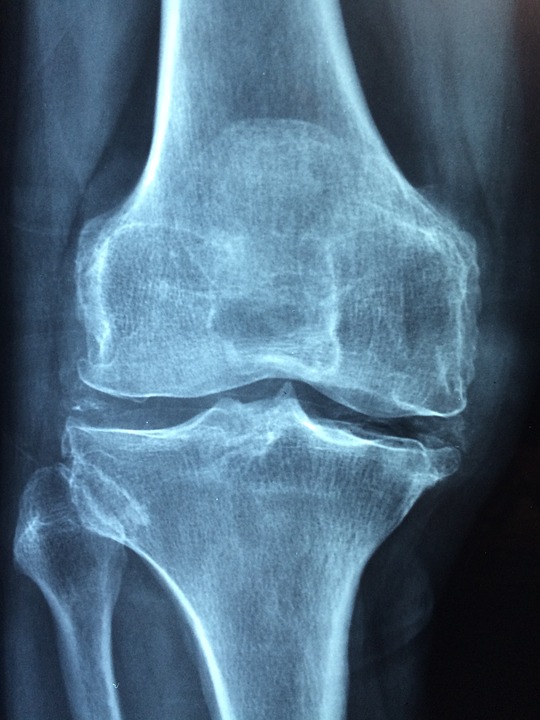

انسانی جسم میں ہر جوڑ دو ہڈیوں سے مل کر بنتا ہے جن کے درمیان ایک جھلی نما چیزہوتی ہے جسے نرم یا کرکری ہڈی (cartilage) کہتے ہیں۔ اس میں سے قدرتی طور پر رطوبت نکلتی ہے جس سے جوڑ چکنا ہوجاتا اور باآسانی حرکت کرتا ہے۔ اگر اس نرم ہڈی کو نقصان پہنچے تو رطوبت کا اخراج متاثر ہوتا ہے جس کی وجہ سے جوڑ ٹھیک طرح سے حرکت نہیں کرپاتا۔اس کے علاوہ جوڑوں میں سوزش (inflammation) بھی ہوجاتی ہے جس کی وجہ سے وہ سوج جاتے ہےں۔ اس کیفیت کو آرتھرائٹس (arthritis) کہتے ہیں۔

اس کی مختلف اقسام ہیں جن میں سے ایک جوڑوں کا پتھرانا یا گنٹھیا نما ورم مفاصل (rheumatoid arthritis) بھی ہے۔ یہ جوڑوں کی وہ سوزش ہے جس میں ہاتھوں‘ پاﺅں اور کہنیوں وغیرہ کے چھوٹے جوڑزیادہ متاثر ہوتے ہیں۔ اگر بروقت علاج نہ کروایا جائے تو گردن اور ریڑھ کی ہڈی کے جوڑ بھی اس کی زد میں آ سکتے ہیں۔ اسے عام زبان میں سوزش والا آرتھرائٹس بھی کہتے ہیں۔